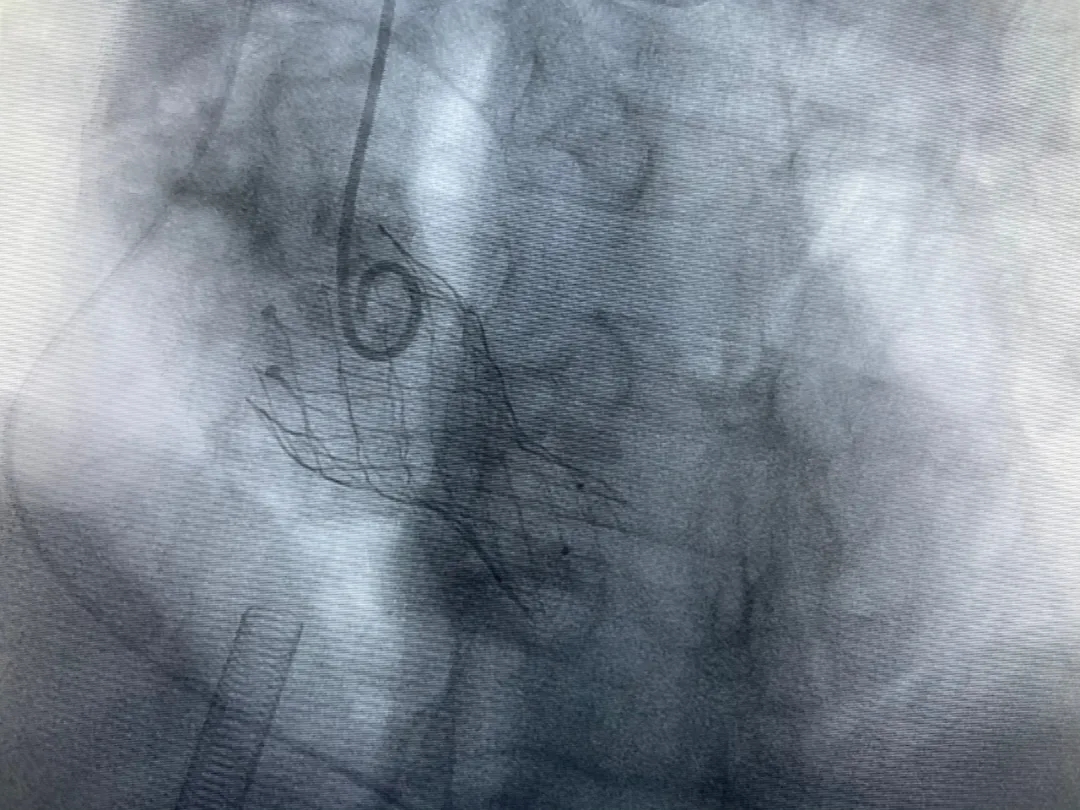

結(jié)合老人病情特點:年齡高、室壁厚、左室腔小、瓣膜鈣化嚴重,術(shù)中球囊擴張和瓣膜釋放過程有循環(huán)崩潰可能;為降低此種風險、最大程度提高手術(shù)成功率,張金洲副院長在術(shù)前組織了由楊金保博士帶領(lǐng)的TAVR團隊多次反復(fù)溝通、討論,制定了各種應(yīng)急處理方案。最終經(jīng)過TAVR團隊的默契配合,手術(shù)歷時2小時,用20#球囊預(yù)擴張后順利植入23#主動脈瓣生物瓣膜,再次后擴后主動脈根部造影顯示:人工主動脈瓣生物瓣位置良好,瓣葉開閉正常;冠脈顯影良好。經(jīng)食道超聲顯示:主動脈瓣葉活動度良好,主動脈跨瓣壓差約35mmHg,未見瓣周漏及明顯返流。出手術(shù)室前老人便已蘇醒,自訴憋悶癥狀完全消失。